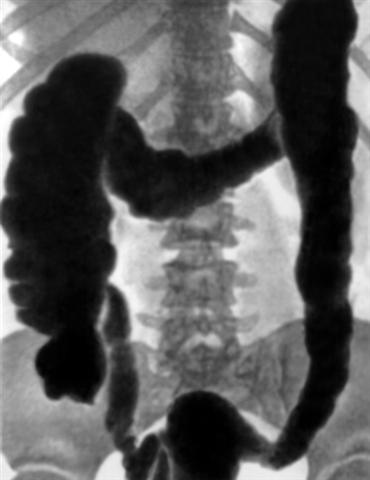

Рис. 1а). Обзорная рентгенограмма толстой кишки при тугом заполнении ее бариевой взвесью в норме.